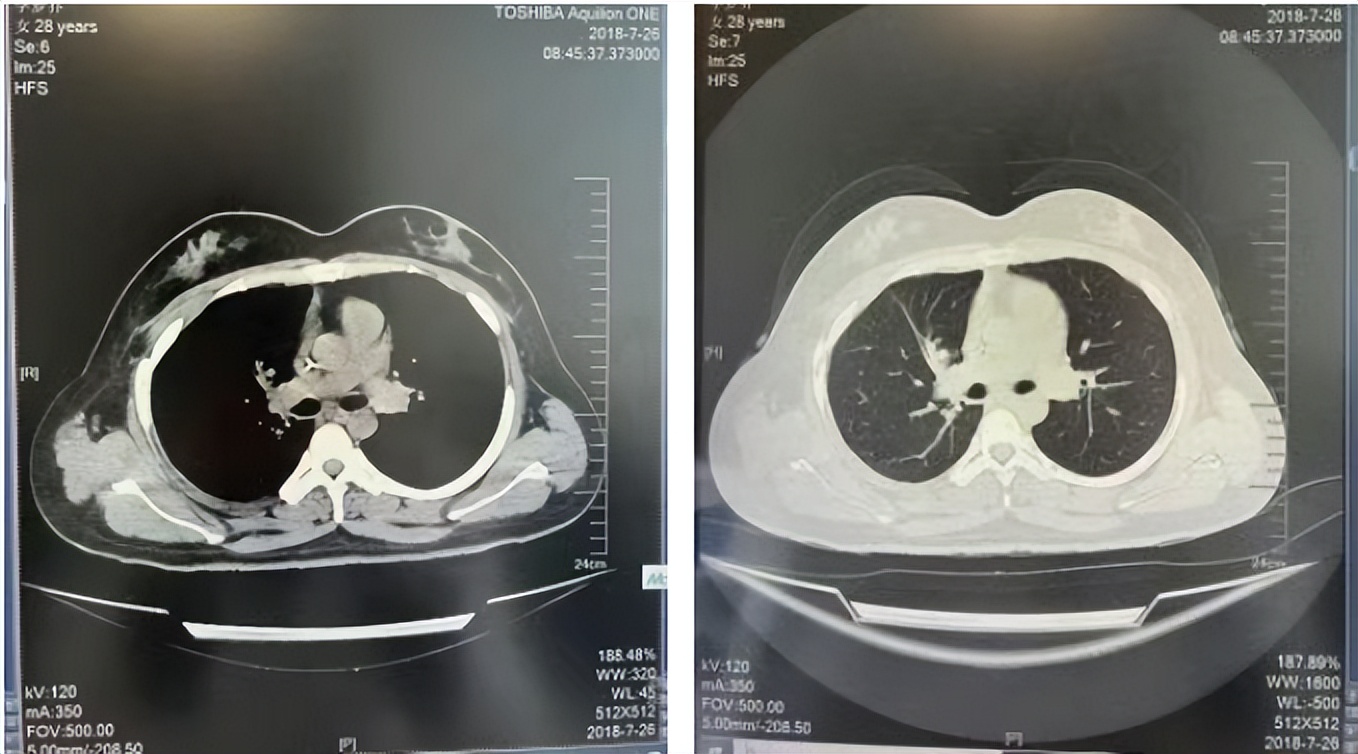

56岁,女性,无吸烟史饮酒史,既往体健。2023年02月患者体检发现肺占位性病变,胸部增强CT:右肺下叶后基底段结节;右侧锁骨上及纵隔内多发淋巴结肿大。PET-CT:右肺下叶周围型肺癌可能性大;1R、2L、3P、4R、4L及7组淋巴结转移可能性大。2023年02月就诊于本院胸外科行超声胃镜下纵隔肿物穿刺活检术,病理:结合免疫组化,符合肺腺癌。行NGS基因检测:EML4:exon20-ALK:exon20融合。PD-L1(克隆号22C3)TPS=55%。

治疗经过:2023年3月27日始行恩沙替尼靶向治疗至今,最佳疗效为PR,末次评效为维持PR。期间出现轻度肝功能异常(DILI 1级),对症处理后好转。截止目前PFS为26个月。

2023年2月20日基线检查

2024年6月复查PR(最佳疗效)

2024年12月复查维持PR

2025年3月复查维持PR